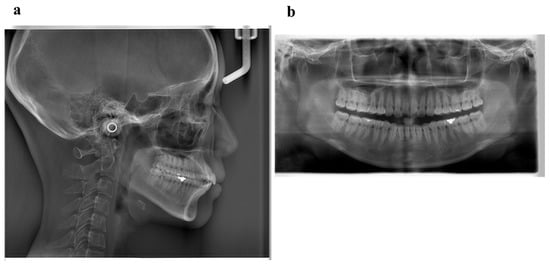

6.4. Treatment Progress

6.5. Treatment Results

6.6. Case Summary

| Measurement | Normal (Japanese Woman) | Pretreatment (29 y 19 m) | Posttreatment (31y 2m) |

|---|---|---|---|

| SNA (° ) | 81.3 ± 2.7 | 80.0 | 80.0 |

| SNB (° ) | 78.6 ± 2.7 | 79.5 | 79.0 |

| ANB (° ) | 2.6 ± 1.1 | 0.5 | 1.0 |

| FMA (° ) | 26.3 ± 4.1 | 24.0 | 24.0 |

| FMIA (° ) | 56.9 ± 6.4 | 52.0 | 61.0 |

| IMPA (° ) | 96.8 ± 6.4 | 104.0 | 95.0 |

| U1-FH (° ) | 112.1 ± 4.2 | 126.5 | 115.5 |

| U1-L1 (° ) | 123.5 ± 5.5 | 105.0 | 125.0 |

| U1-A-Pog (mm) | 6.2 ± 1.5 | 11.2 | 4.6 |

| L1-A-Pog (mm) | 3.0 ± 1.5 | 8.1 | 2.3 |

| Gonial angle (° ) | 118.8 ± 6.1 | 117.5 | 117.5 |

| E-line: Upper (mm) | 1.4 ± 2.0 | −0.5 | −2.0 |

| E-line: Lower (mm) | 1.4 ± 2.0 | +0.3 | −0.7 |